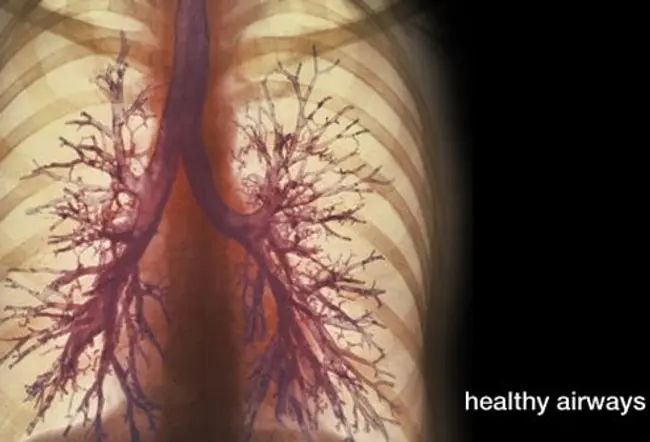

COPD是慢性阻塞性肺病的縮寫。COPD是一種肺部疾病,由導致呼吸問題的肺部氣道阻塞引起。盡管 COPD是一種進行性疾病,但早期診斷和治療可能會減緩其進展。

隨著時間的推移,肺組織受損會導致肺部發生物理變化,并且氣道會被粘稠的粘液堵塞。由于這種肺組織損傷,順應性(肺組織擴張的能力)變弱。肺部順應性或彈性減弱意味著氧氣無法到達肺部發生氧氣和二氧化碳交換的空氣空間。這一切都會導致咳嗽以清除粘稠的粘液,最終導致呼吸困難。

呼吸急促是COPD的主要癥狀。它發生在日常活動中,是由氣道阻塞或阻塞以及肺泡受損或破壞引起的,肺泡吸收氧氣并釋放二氧化碳。其他COPD癥狀可能包括喘息、胸悶和慢性咳嗽。受影響的人可能容易疲倦,經常感冒和流感感染,并產生過多的粘液或痰液。慢性阻塞性肺病的癥狀會慢慢惡化,患有慢性阻塞性肺病晚期癥狀的人可能: